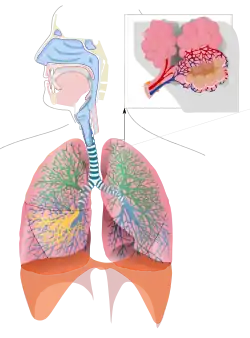

Inhalation is a major route of exposure that occurs when an individual breathes in polluted air which enters the respiratory tract. Identification of the pollutant uptake by the respiratory system can determine how the resulting exposure contributes to the dose. In this way, the mechanism of pollutant uptake by the respiratory system can be used to predict potential health impacts within the human population.

The deposition of particulate pollutants into the lungs is necessary before the particles can travel through the mucus into the lung tissue. There are four mechanisms of deposition: interception, impaction, gravitational settling, and Brownian diffusion. Interception happens when a particle is removed after brushing up against an obstacle. Impaction happens when the particle collides into the surface of the respiratory tract due to the high inertia. Gravitational settling is influenced by the force of gravity which causes the particle to settle on the respiratory tract. Brownian motion causes the random collision of gas molecules against the particle, until the particle goes into the respiratory tract.

Prediction of the location of particle deposition into the respiratory tract depends on the size and type of particle. Coarse particles, originating from natural sources such as dust, sand and gravel, tend to deposit in the nasal-pharyngeal region. Fine particles, derived from anthropogenic sources such as fossil fuels and smoking, typically deposit in the pulmonary region. Most gas exchange occurs in the pulmonary region due to the alveoli, which contain a large surface area.

Scientists have identified a positive correlation between particulate matter concentrations being the causative factor of respiratory and cardiovascular disease. Particulate matter may also be responsible for as many as 20,000 deaths annually, and exacerbation of asthma. Quantification of dose, determining total number of particles deposited in the pulmonary region, surface area of particles, acidity of particles, and shape are important in determining health impacts. A larger surface area will cause more toxins to be available for absorption into the mucus. Particles such as asbestos have the ability to become permanently enlodged into the alveoli causing cancer in some cases.

Soluble particulate matter can be highly detrimental to the respirator tract because of their ability to dissolve into the mucus or surfactant layer. This can irritate tissues by changing pH, and transport into the rest of the body or gastrointestinal tract. Insoluble PM, such as lead particles, deposit in the nasal-pharyngeal region and can be cleared by blowing, sniffling, or spitting. However, swallowing can cause the particles to deposit into th GI tract. Particles in the tracheobronchial region can be cleared by the cilia, which will move particles into the mucus. Insoluble particles that enter the pulmonary region cause swelling of the alveoli, coughing, and shortness of breath.